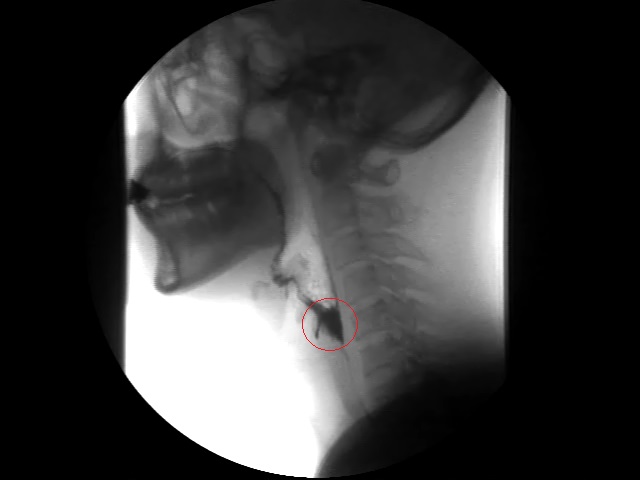

In our study of the motion analysis of hyoid bone observed from X-ray video clips, the trajectories can be thought of as 2D functional data (see Figure 1, the background of the data will be discussed in Section 3). There exists obvious misaligned problems for those curves in both vertical and horizontal variation. Usually, curve alignment is performed as a preprocessing technique and the clustering is conducted afterwards. This way is not efficient, since a subject belonging to which cluster is closely related to how it unfolds its progression pace. Another challenging problem for this study is that the heterogeneity of regression relationships among different groups. It consists in both the potential time warping for curves corresponding to the subjects and the subjects’ scalar variables such as initial level of disease, gender, age and the characteristics of those trajectories themselves, like motion time, average speed and range of motion. Therefore, simultaneous curve registration and clustering by considering all those factors seems to be a better way for modeling the functional data.

The application to a real data is to cluster the normal people and the patients with stroke by studying their hyoid bone motion as well as the other scalar variables. Two groups, one for normal people and the other for patients, are included. Figure (1)(a) shows one frame from a X-ray video clip. The position of hyoid bone is tracked in each frame by a semi-automatic programme developed in Kim et al., (2017). The raw data before being preprocessed are shown in Figure (1)(b). There are 15 subjects in each group. The scalar variable we choose is the size of Pyriform Sinus Residue (see its position in Figure A.6). Regarding to those 2D curves, we firstly carry out the preprocessing procedures like multi-dimensional shift, scaling and rotation using the package of GPA. While modeling those curves, we assume the warping function be a smooth nonlinear deformation produced by an increasing spline and the random vector be a Brownian bridge observed at discrete anchor points. B-spline basis functions are utilized for modeling the mean curves. The covariance function for the amplitude variance is the Matern covariance function.